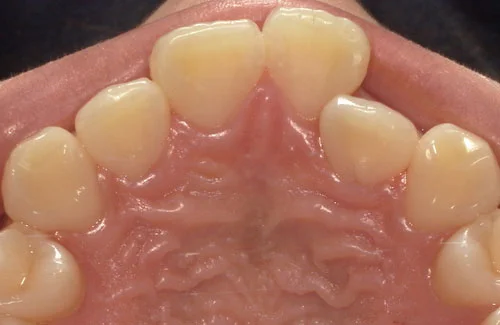

<症例7>歯がガタガタで噛み合わせが悪くお悩み

抜歯無し・マウスピースのみで矯正した症例です。

もともと歯列弓が非常に狭く、V字に近い形をしていたので噛み合わせも非常に不安定でした。

また、下顎前歯部がかなり上の方に生えていたため、下の前歯が上の前歯を突き上げてしまい出っ歯の状態になっていました。

現在では見た目はもちろん、臼歯の噛み合わせも改善しております。

奥歯の患者様も大喜びでした。

患者様と症状

主訴:歯のガタガタ、噛み合わせが悪い

性別・年齢:20代女性

問題点:叢生(重度)、V字歯列弓、ディープバイト

診断:前歯部の叢生を伴うアングルⅠ級、骨格性Ⅰ級の不正咬合

主なリスク:臼歯の移動に伴い一時的に咬合しにくくなる、歯肉退縮

症状:叢生(そうせい) 過蓋咬合(かがいこうごう)

治療内容

治療期間:1年10ヶ月

治療費用:990,000円(税込)

プラン:Full2プラン

抜歯:無し

再診治療費:無し

追加治療費:無し

保定装置費:無し

治療前後の写真